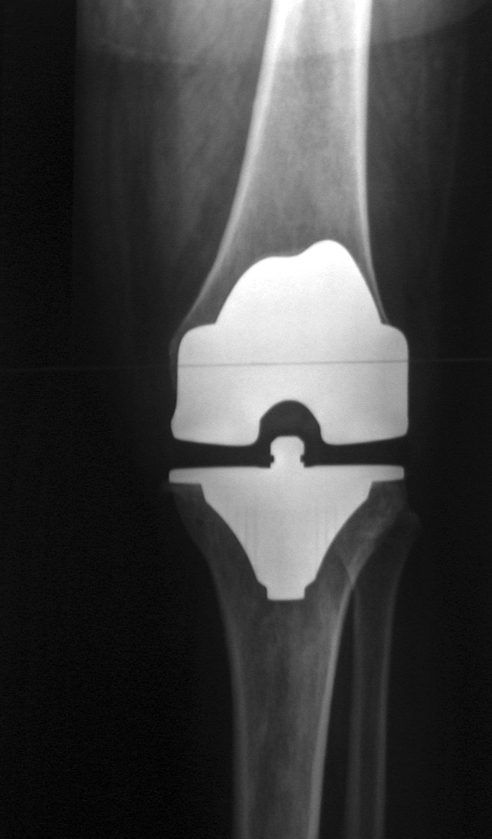

Often the question is asked by individuals suffering with some “joint” pain is “do I or will I need a joint replacement surgery?” This question is asked because these procedures (hip, knee, and shoulder) are quite common in this country.

Just what does success look like? Well, this will be different from person to person, BUT in most cases success is: less pain medication, no or fewer injections, increased mobility and freedom to do pleasurable activities, and NO joint replacement. But the doctor said I would need a replacement in the future? Ok, but what do you want to do with all those years before that may happen?